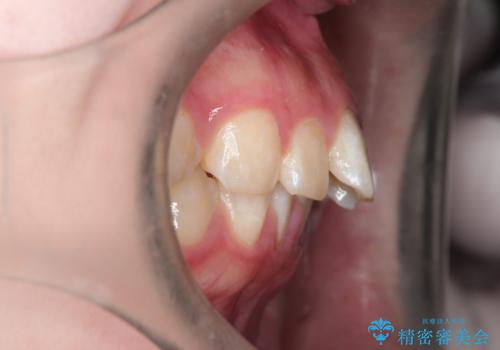

- 前歯のガタガタが気になるとのことで来院されました。

上顎の前歯の叢生があったのと、下あごの前歯が通常より1本欠損(先天欠損)していました。

上顎の歯と歯の間をわずかに削りスペースをつくり、並べる計画としました。インビザライン治療を選択されました。